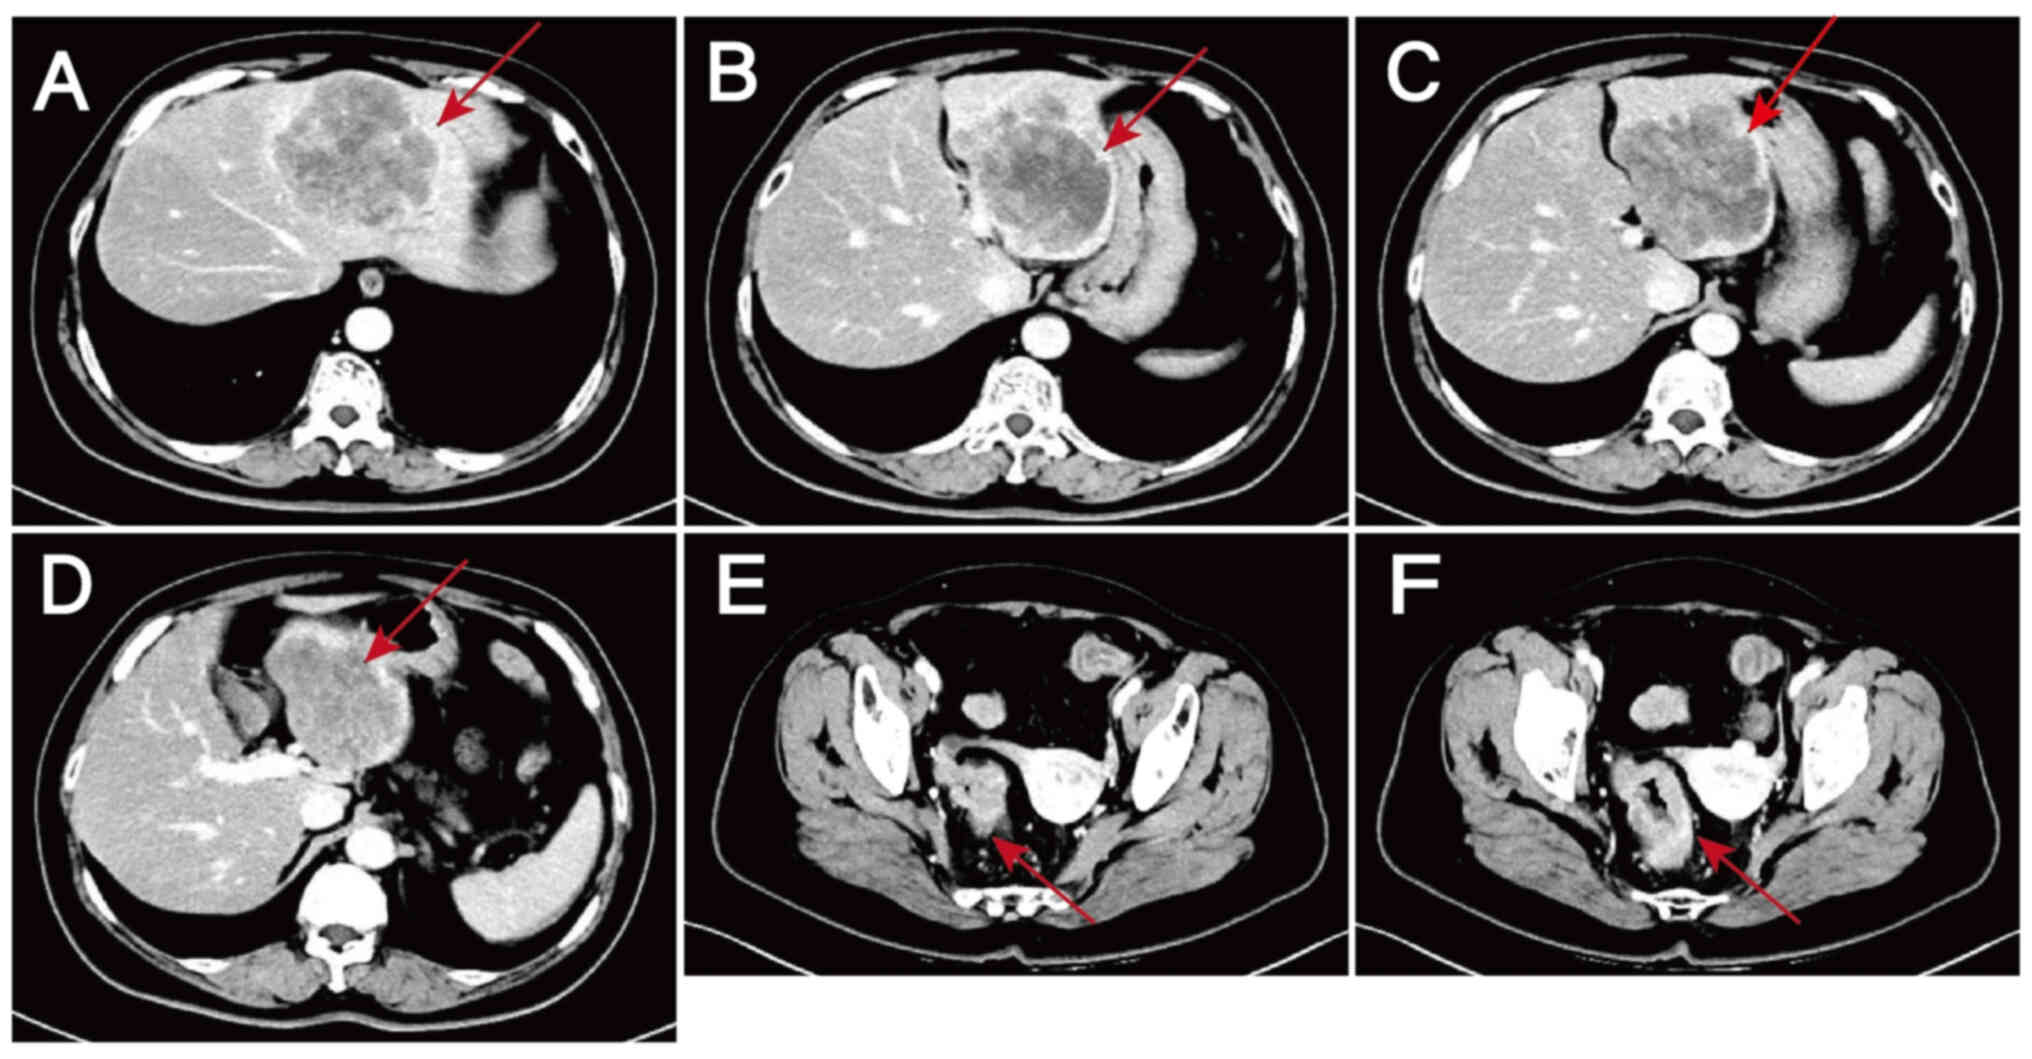

Initial assessment of the lesions by

computed tomography on October 15, 2023. (A-D) Metastatic liver

lesions: Slightly hypodense shadows are visible in the S2, S3 and

S4 segments of the liver, suggestive of metastasis. (E and F) Colon

lesions: Thickening of the sigmoid-rectal wall and enlargement of

the peripheral lymph nodes are indicative of malignancy. Lesions

are indicated by arrows.

Figure 1.

Initial assessment of the lesions by computed tomography on October 15, 2023. (A-D) Metastatic liver lesions: Slightly hypodense shadows are visible in the S2, S3 and S4 segments of the liver, suggestive of metastasis. (E and F) Colon lesions: Thickening of the sigmoid-rectal wall and enlargement of the peripheral lymph nodes are indicative of malignancy. Lesions are indicated by arrows.

A 60-year-old woman with complaints of abdominal pain and passage of bloody stools was admitted to Hebei General Hospital (Shijiazhuang, China) in October 2023. Contrast-enhanced scans of the abdomen and pelvis revealed wall thickening in the sigmoid colon and rectum, enlarged lymph nodes in the surrounding area suggestive of malignancy, and low-density shadows in the S2, S3 and S4 segments of the liver that were thought to be metastases (Fig. 1). Colonoscopy suggested rectal cancer, and a tissue biopsy revealed moderately and well-differentiated adenocarcinoma with necrosis (Fig. 2). Magnetic resonance images revealed liver metastases in the S2, S3 and S4 segments and two enlarged lymph nodes, one anterior and one posterior to the portal vein (Fig. 3). Digestive tract tumor marker levels, including carcinoembryonic antigen, carbohydrate antigen (CA)242 and CA724, were all higher than normal (Fig. 4). NGS of a biopsy specimen obtained by colonoscopy suggested that KRAS, NRAS and BRAF were WT (Figs. S1 and S2). It also revealed that ERBB2 (HER2) had a mutation abundance 8.3-fold higher than the reference level, suggesting possible resistance to panitumumab and cetuximab. In addition, TP53 exon5c.399del had a mutation abundance of 31.61%, suggesting microsatellite stability. The NGS was performed by Novogene Bioinformatics Technology Co., Ltd. DNA extraction and library preparation was performed using the Qiagen QIAamp DNA FFPE Kit (Qiagen, GmbH) and Agilent SureSelect XT HS2 (Agilent Technologies, Inc.), respectively. Sample quality was assessed by pathological analysis of tumor cell content, nucleic acid quality assessment (total DNA amount, DNA degradation degree and total pre-library amount) and sequencing quality assessment (average sequencing depth, coverage uniformity, genome alignment rate and base quality Q30 proportion). The hybridization capture method was used, and the read length and sequencing direction were double ends of 150 bp and double-end sequencing, respectively. The sequencing platform and sequencing kit were the Illumina NextSeq 550 and Illumina NextSeq 550 High Output kits (Illumina, Inc.), respectively. Final library loading concentration was 1.2–1.8 pM. The software used for the analysis included CNVkit (version 0.9.9; University of California), GATK Mutect2 (version 4.1.8.1; Broad Institute of MIT and Havard) and PierianDx (version 7.3; Velsera, Inc.).

Following discussions among the multidisciplinary team and considering the patient's preference for surgery, neoadjuvant therapy was initiated, with plans to proceed to surgery for the primary CRC lesions and liver metastases if the treatment was effective. After obtaining informed consent, the patient was treated with two cycles of a modified FOLFOX6 regimen based on a body surface area of 1.66 m2, comprising oxaliplatin 140 mg + leucovorin calcium 600 mg + fluorouracil 0.625 g by intravenous injection + fluorouracil 3.75 g. This regimen was administered by continuous intravenous drip on 13 days post admission and 28 days post admission. However, after the two cycles, no reduction in the size of the tumor lesions was evident (Fig. 5) and the tumor marker levels remained elevated (Fig. 4), suggesting poor treatment efficacy.

Lesions after 1 cycle of chemotherapy as evaluated by computed tomography on November 10, 2023. (A-D) Metastatic liver lesions: No marked change is visible compared with those on October 15, 2023. (E and F) Colon lesions: Thickening of the sigmoid-rectal wall is slightly less severe than that on October 15, 2023, but no changes are evident in the surrounding enlarged lymph nodes.